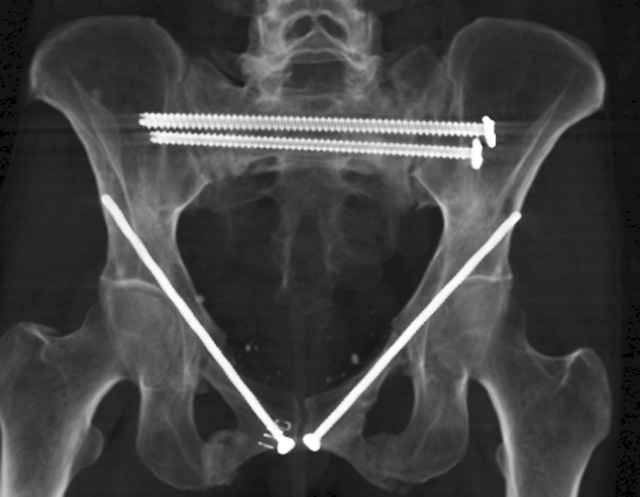

Here are a recent patient’s example slides...

54 yo Female Fell c/o Pain

Initial Films

?Instability on Exam - Limited by Pain

NonOp Initial Mgmt

3 Months After Fall

Continued Pain & Immobility

(+) Instability to Compressive Manual Exam

Pelvic CT Scan - 3 Months After Fall

Sacral Injuries

Ramus Fractures

Percutaneous Fixation

(B) Ramus-Retrograde

2 TransIliac-TransSacral

Upper Segment

mlcr